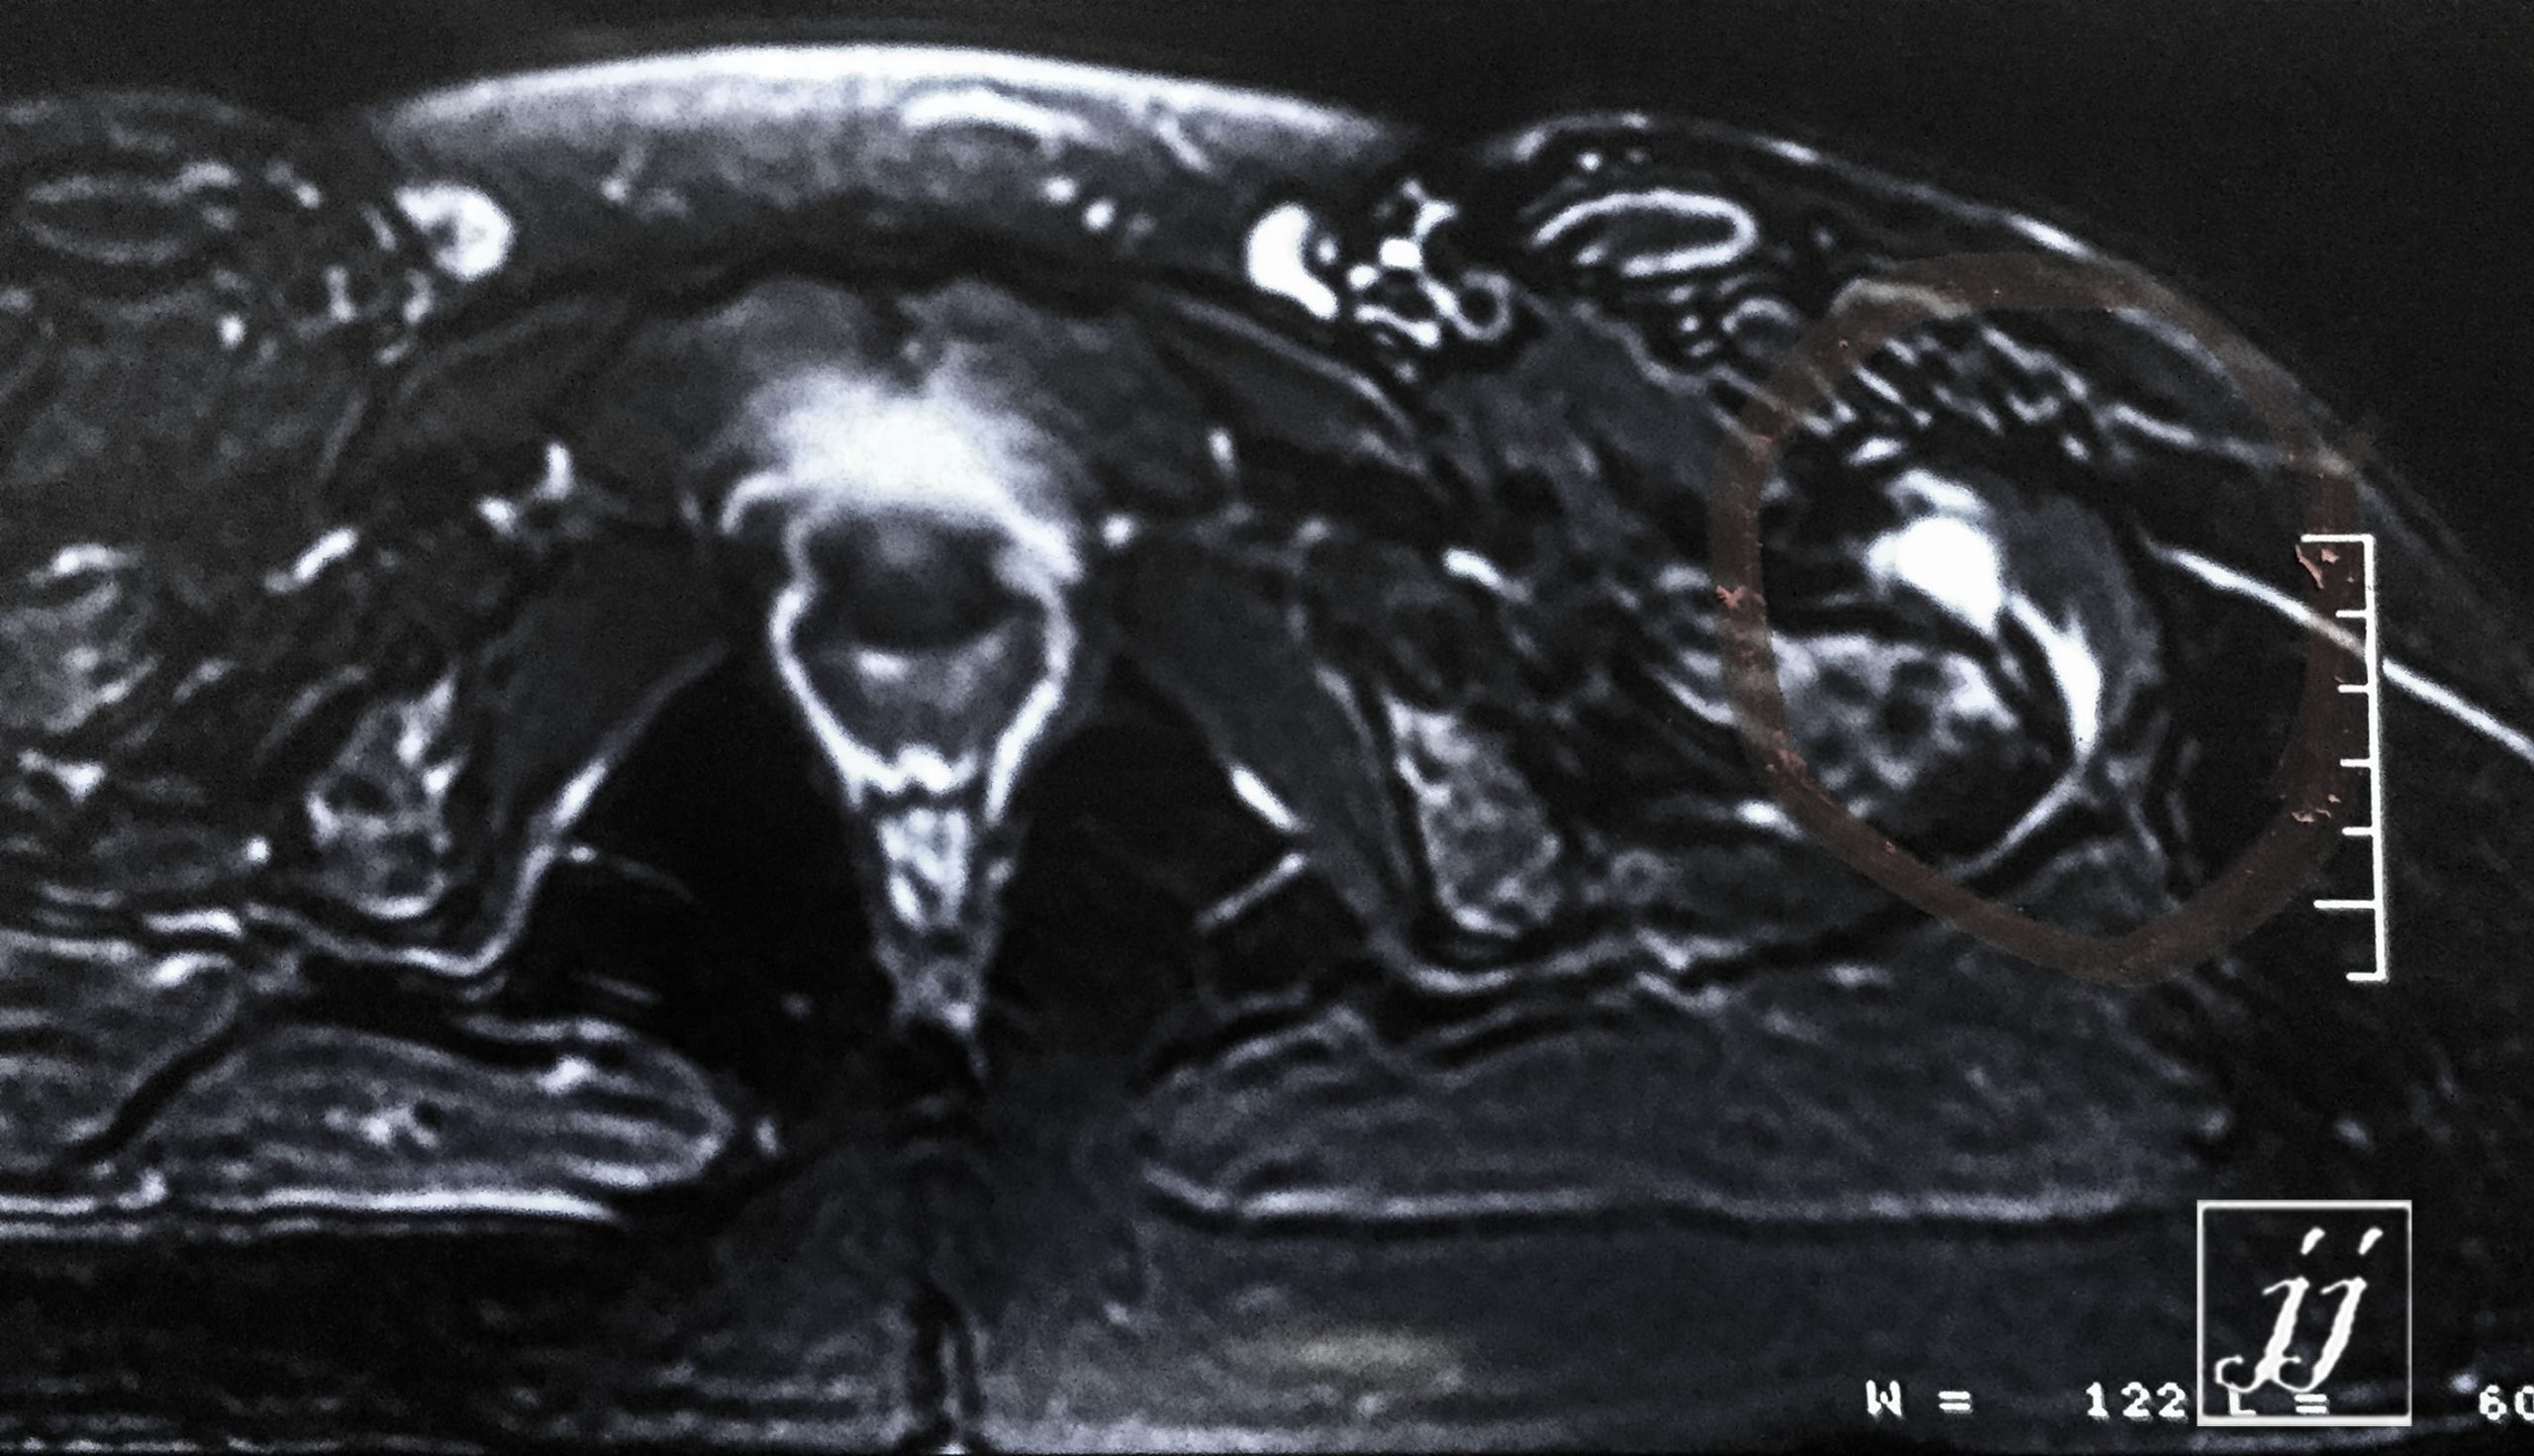

MSK- left inguinal aneurismal artery (5)